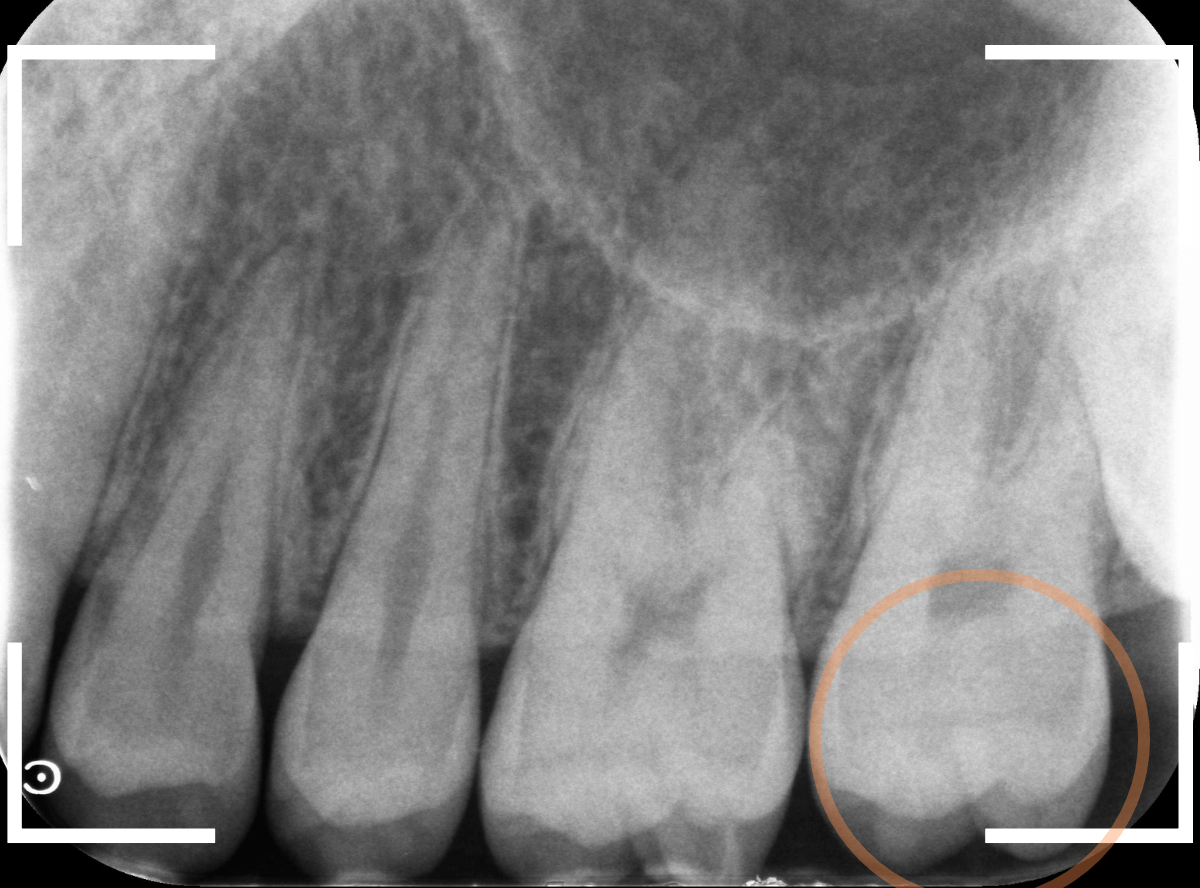

Case.2 レントゲンで判別しづらい、小窩裂溝う蝕

今回は、レントゲン写真で判別しづらい、小窩裂溝う蝕です。

レントゲン写真で確認します。

〇部が虫歯の部分です。

左側の歯はうっすらと黒い影が見えますが、わかりづらい写り方です。

虫歯の部分を少しずつ削りながら、虫歯を確認します。

左側の歯はかなり虫歯が広がっているのがわかりますね。

典型的な、内部で広がる小窩裂溝う蝕です。